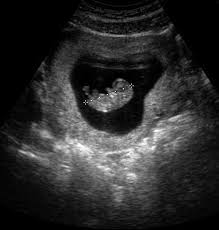

1.hét: Anyu,még csak 8 mm-es vagyok,de megvan az összes fontos szervem.Imádom hallgatni a bársonyos hangodat,mindig amikor hallom,megmozdul az összes kicsi csontom a picinkó testemben.A szíved dobogása számomra a leggyönyörűbb melódia.

2.hét: Anyu,ma megtanultam,hogyan kell szopni a hüvelyk ujjacskámat,ha most látnál biztosan azt mondanád hogy teljesen úgy nézek ki mint egy kisbaba.Olyan jó meleg van idebenn.

3.hét: Tudod mi Anyu? Kislány vagyok.Remélem örülsz neki.A te kislányod vagyok.Én is mindig veled sírok csak te nem hallasz engem.

4.hét: Anyu,már a hajam is elkezdett nőni,csak kár hogy még olyan kicsi szálak,de azt hiszem hasonlít a tiédre.És már tudom mozgatni a kicsi fejecskémet,az ujjacskáimat is,de a lábacskáimat és a kezeimet is csak egy kicsit tudom mozgatni,de erre még bőven van időm,nem gondolod?

5.hét: Anyu,te ma orvosnál voltál? Ő csak hazudott neked mikor azt mondta hogy még nem vagyok baba. Anyu hiszen én a te babád vagyok,és nagyon szeretlek.És Anyu??? Mit jelent az hogy elvetélés?

6.hét: Anyu,én megint hallom az orvost,miért olyan gonosz hozzád? Miért merészkedett be a házacskámba? Anyu,ő azt mondta hogy tű...mi az a tű? Anyuuuuu.Ez nagyon éget,és nagyon fáj,mondd már meg neki hogy hagyja abba. Anyu én nem akarok elmenni,nem akarok tőled elmenni,mégis miért csinálja ezt?! Kérlek Anyu,segíts,ez nagyon fáj,Anyuuuu neee!!!

7.hét: Anyu,jól vagyok...már az égben vagyok, a Jézuska a karjaiban tart,nagyon hiányzol nekem,vissza akarok hozzád menni,még ha tudom is hogy ez lehetetlen.Már elmagyarázták nekem mit jelent az hogy elvetélés.Anyu,mondd miért nem akartál engem? Hiszen én téged mindennél jobban szeretlek.De te miért nem szeretsz engem? Még ha ez is történt,én akkor is a te kis angyalkád maradok örökre,kérlek Anyu,már soha ne akarj elveszíteni egy Angyalkát! :( ♥